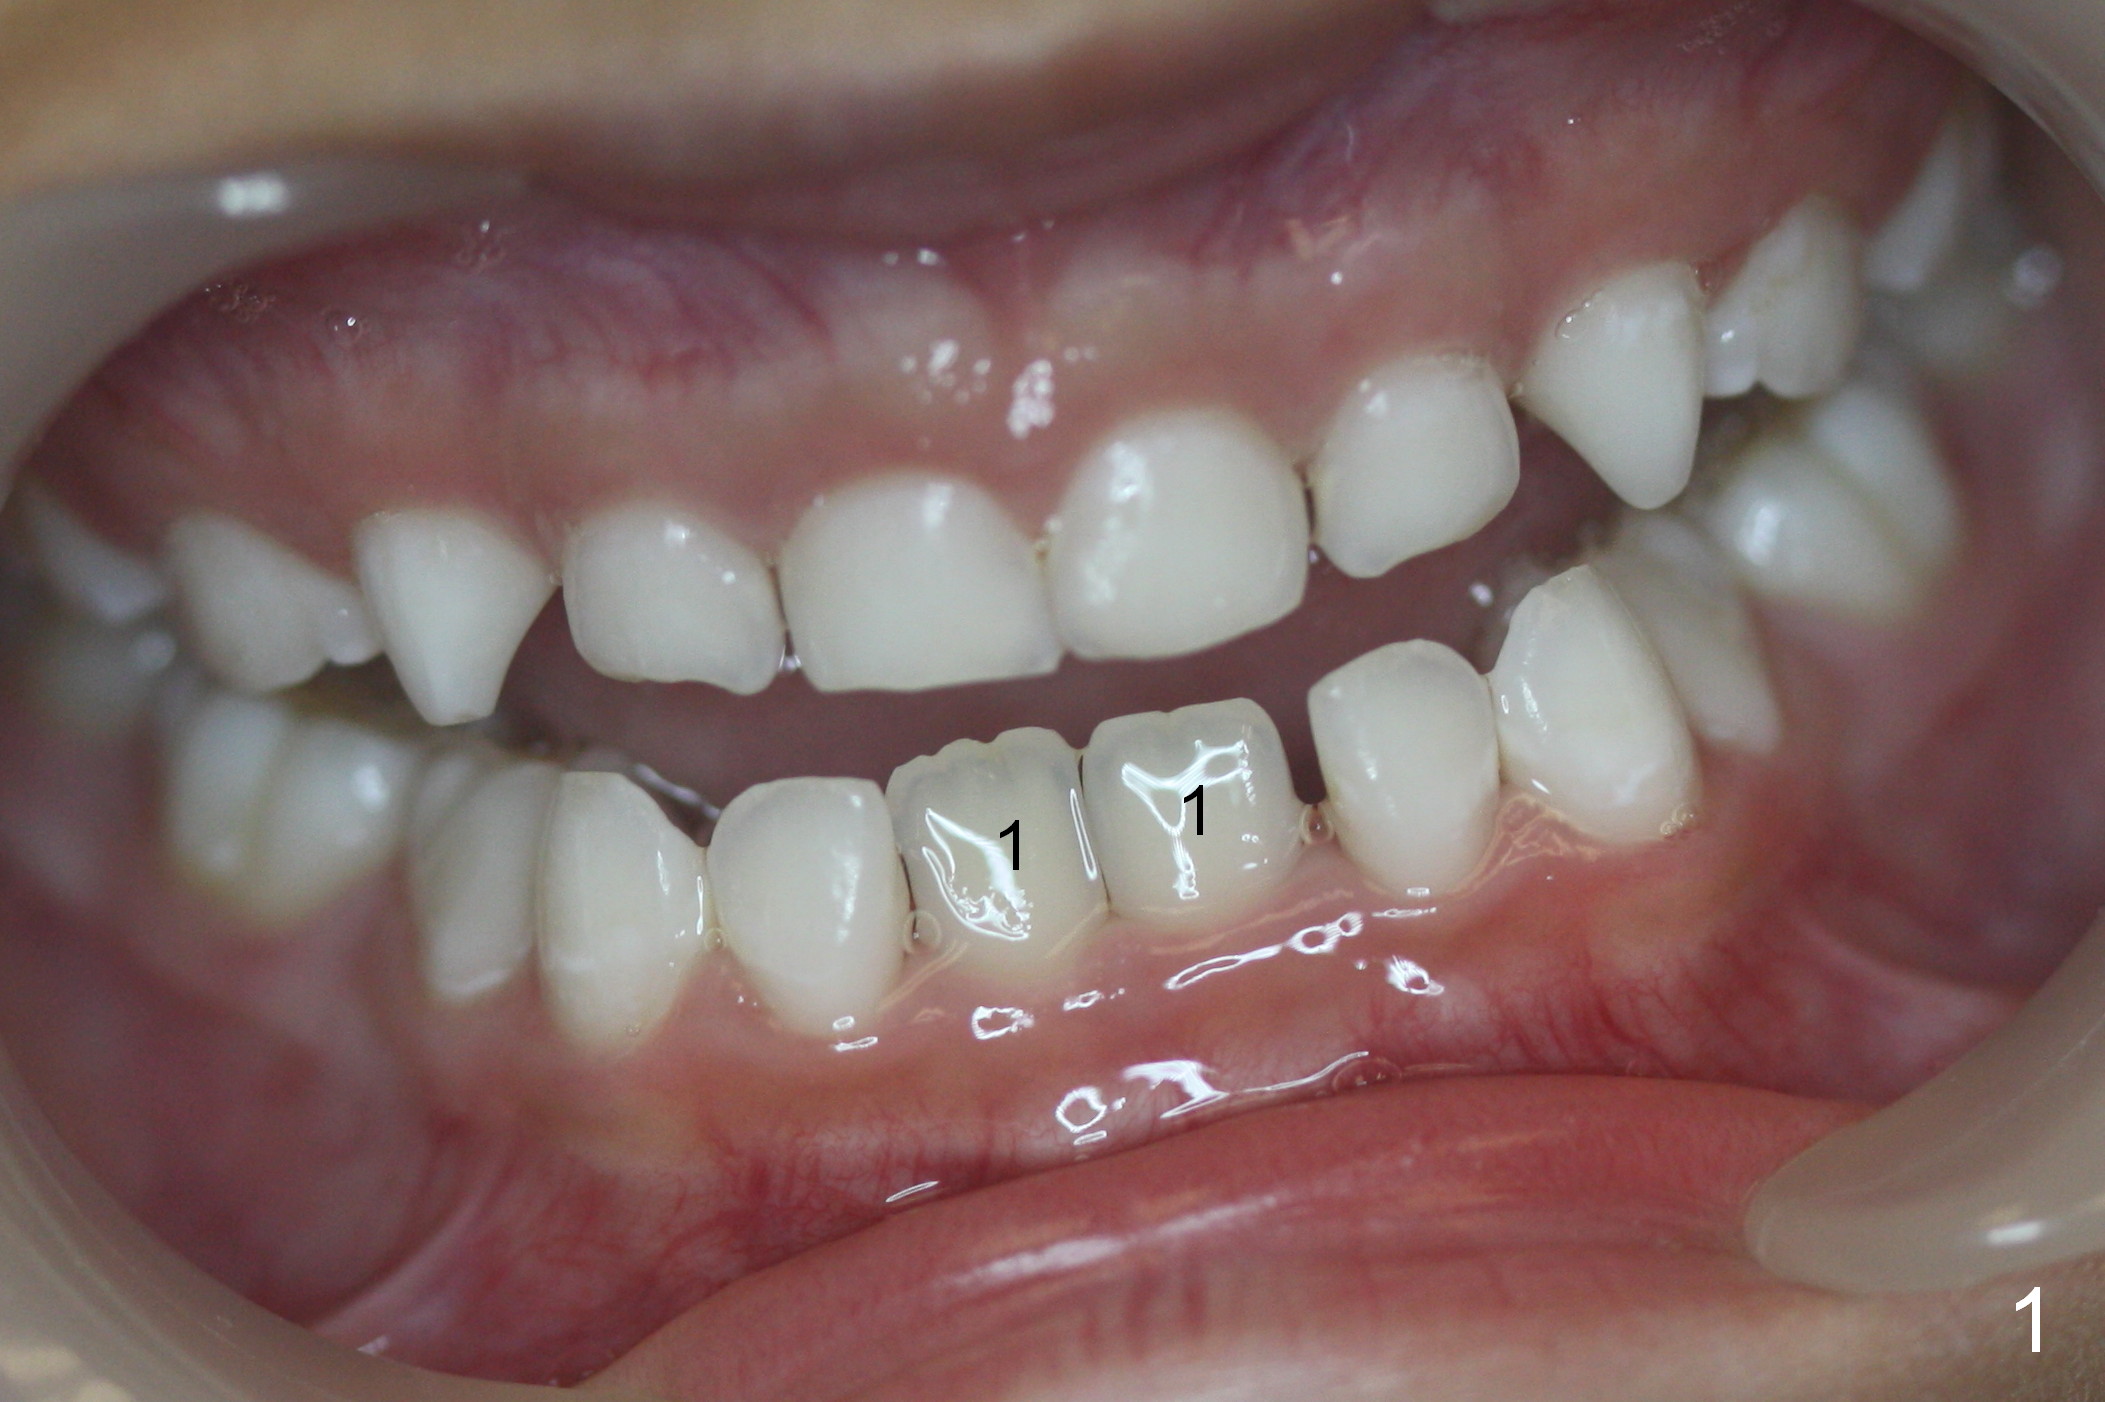

Deciduous Anterior Cross Bite

Unlike his brother, Andrew (7 years 10 months old) does not have missing teeth (Fig.1-3). But there is anterior cross bite involving the deciduous teeth (Fig.2: B, C). It appears that the permanent lower central incisors (Fig.1: #1) have erupted into the normal position (Fig.2). It is hoped that the anterior cross bite is a temporary phenomenon.